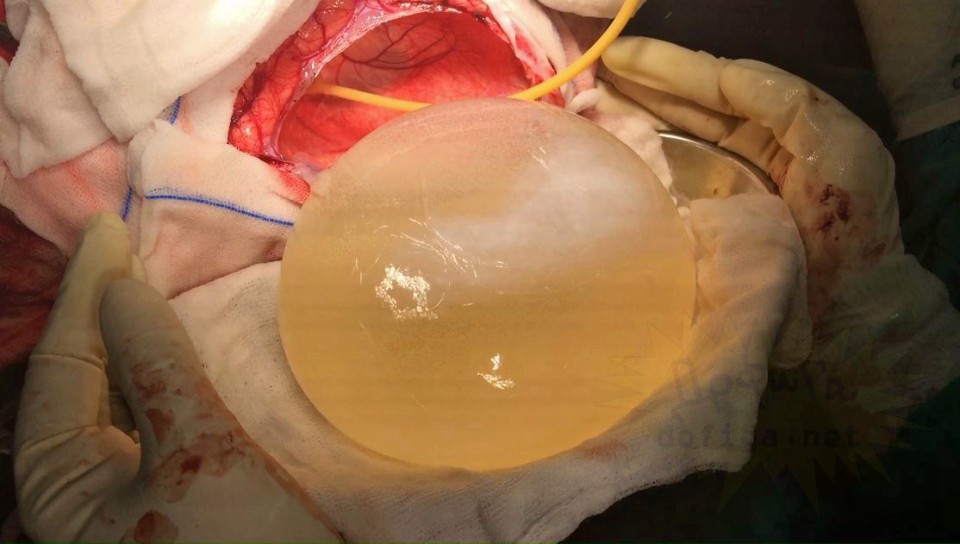

gif_animation インドにて、12歳の女の子の身体(脳部分)から、寄生虫の卵、675gが取り出された。頭痛に苦しんでいたという女の子。感染源は不明である。[7]images